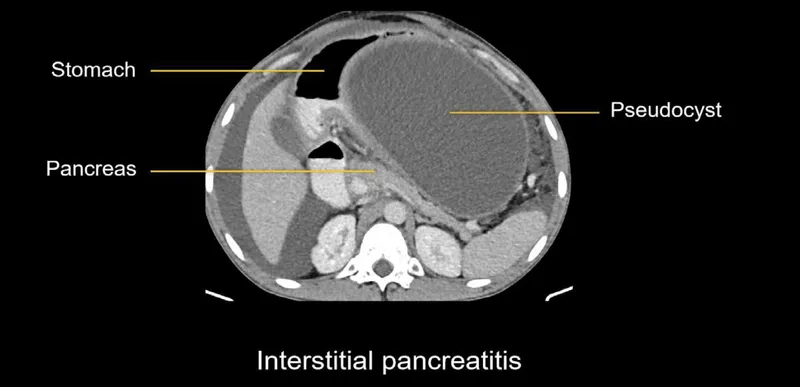

- Imaging: US (initial, for gallstones); CECT Abdomen (gold standard for severity/necrosis, after 48-72h if severe).

- CTSI (CT Severity Index): Balthazar grade + Necrosis. Max 10 (score ≥7 severe).

- Local: Pseudocyst (>4 wks): Drain if symptomatic, >6 cm, or complicated. Walled-Off Necrosis (WON) (>4 wks): Step-up approach (drainage then necrosectomy) if infected/symptomatic.

- Contrast-Enhanced CT (CECT) is the imaging modality of choice for detecting necrosis and complications.

- Pancreatic pseudocyst is a common late complication, typically managed if symptomatic or large.